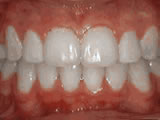

Spacing of teeth

Before

AfterPatient was bothered by the spaces between his teeth. Braces closed the spaces and gave him an ideal bite in 24 months. Special glued-in retainers help keep the spaces closed.